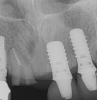

Fig 7. Radiograph showing the patient’s multiple implant restorations.

Figure 7